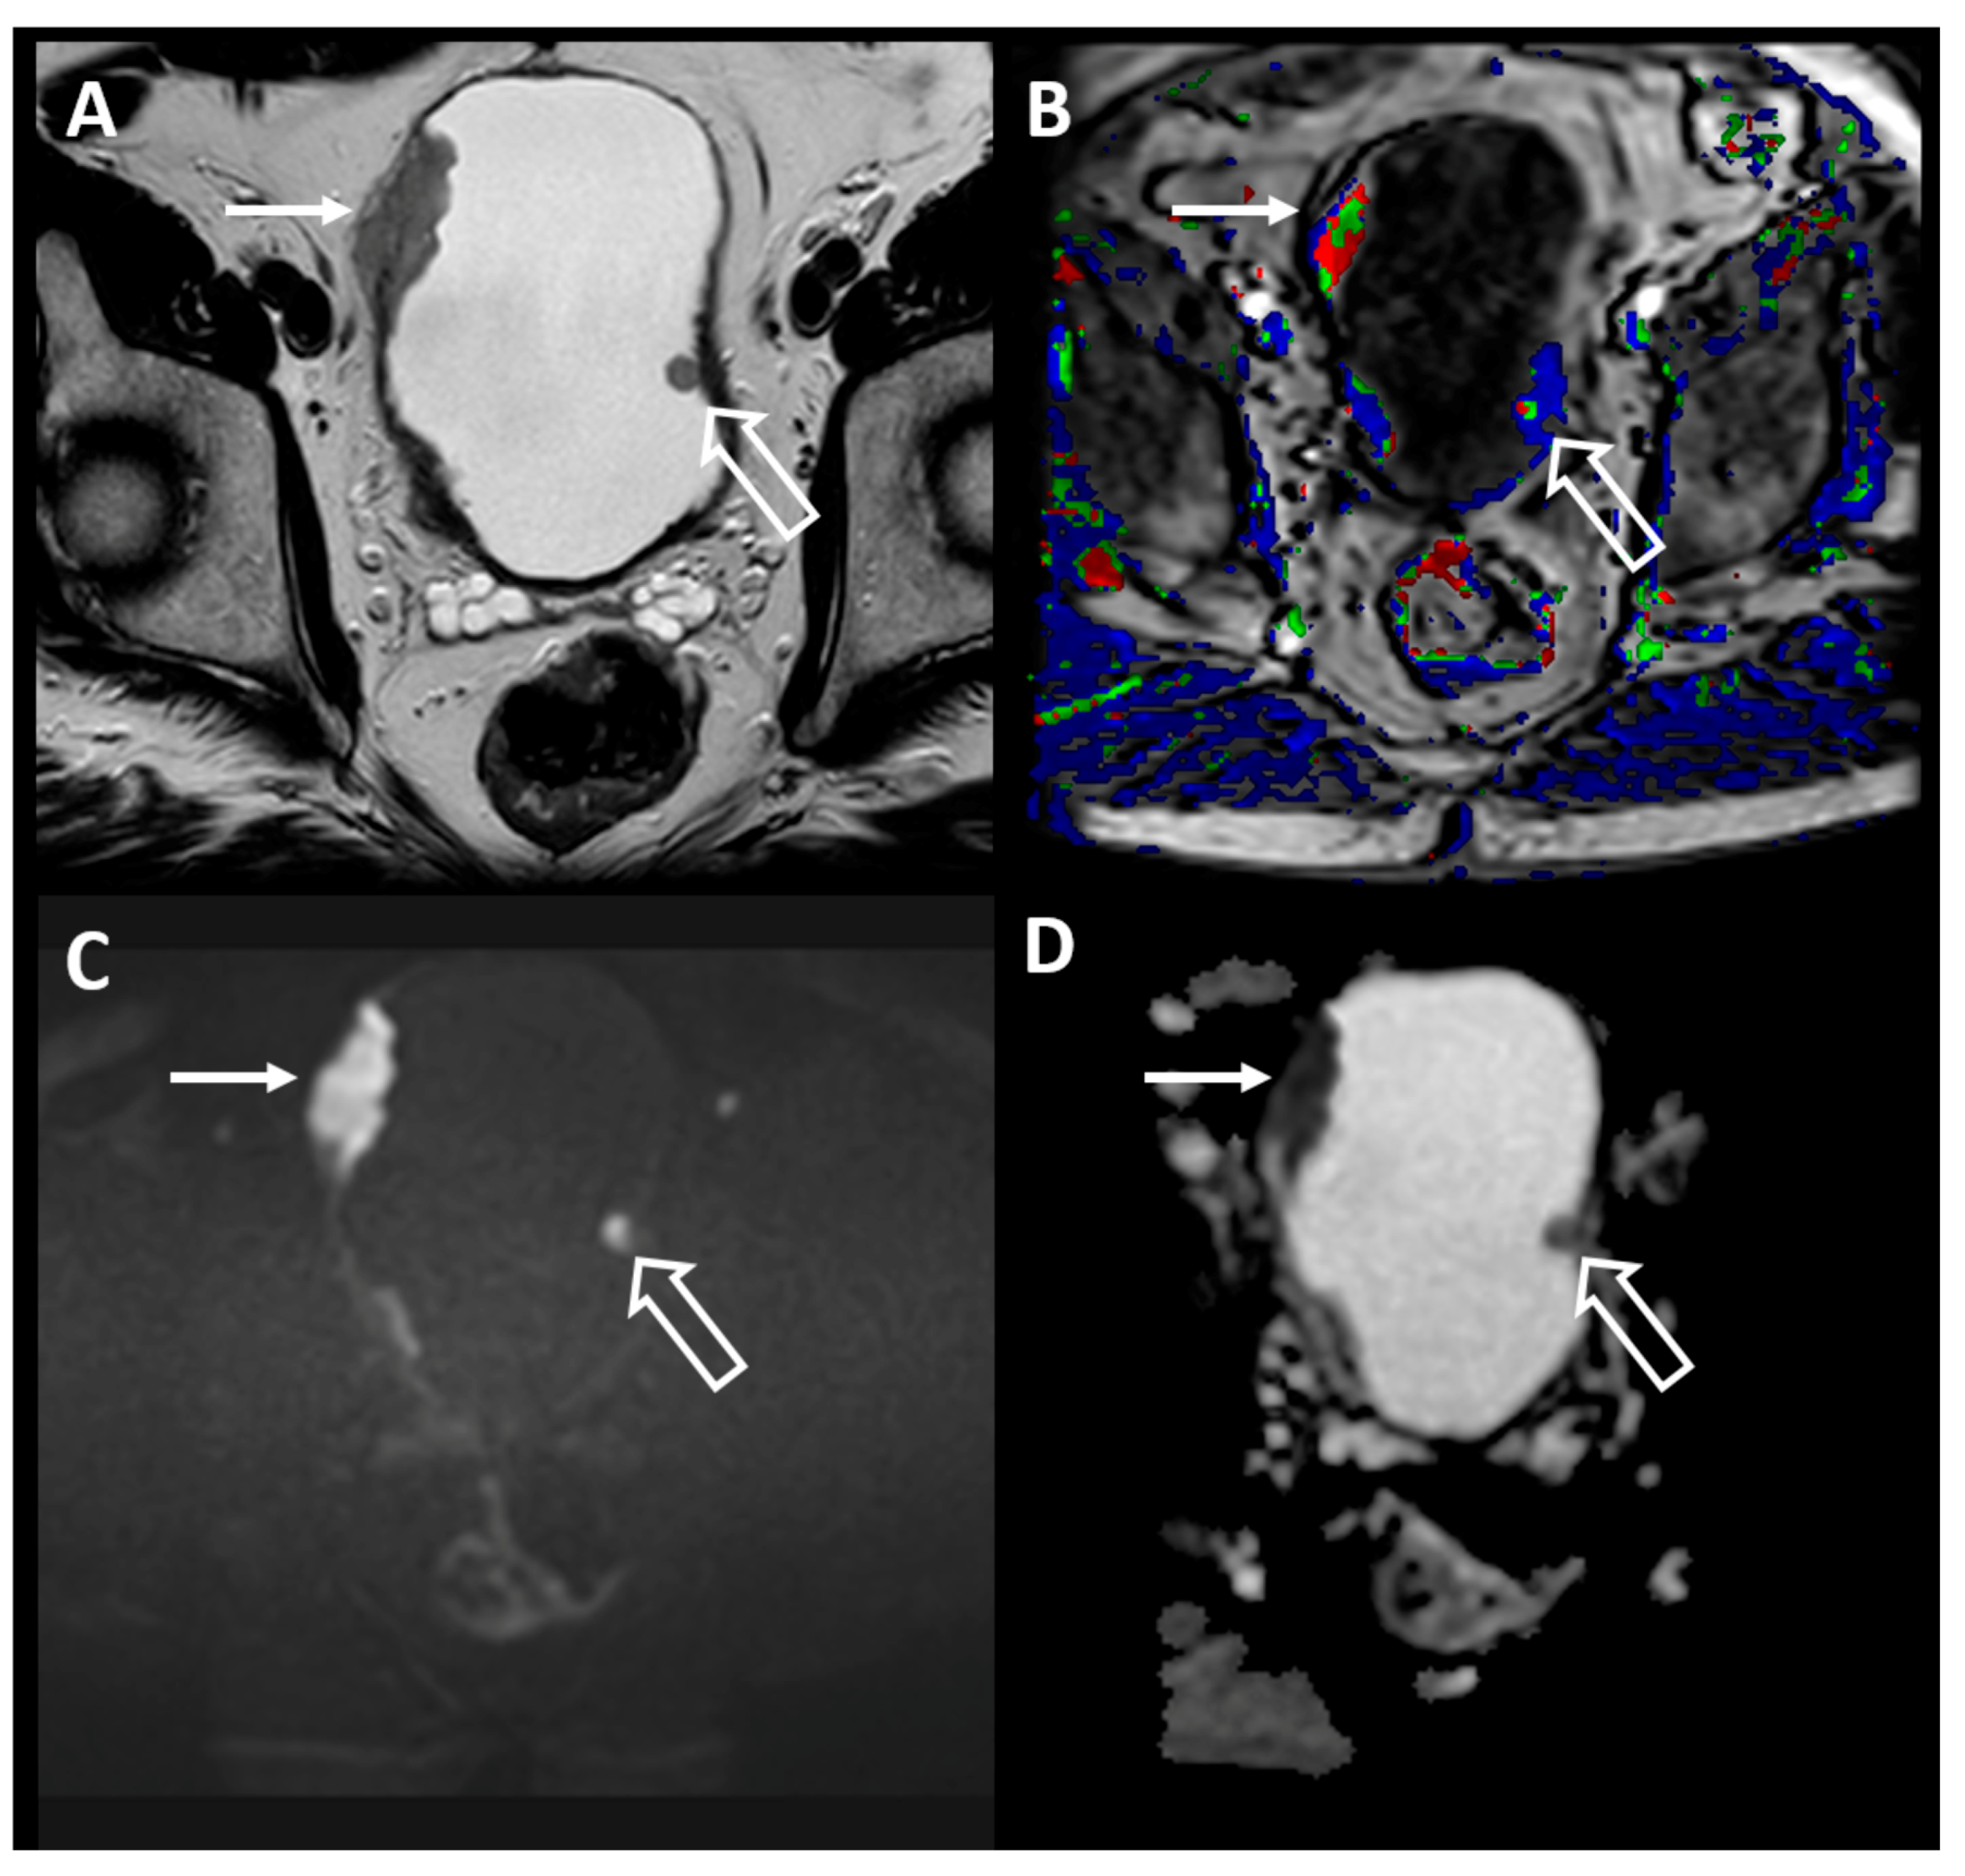

Accounts for around 3-8 of all bladder cancers. The role of newer MR imaging. Whole-body CT is the primary imaging technique for detecting metastases in affected patients especially those with muscle-invasive disease.

Leiomyosarcoma is a rare type of cancer that affects smooth muscle tissue. MRI can distinguish muscle-invasive from non-muscle-invasive tumors with accurate local staging. Magnetic resonance MR imaging and computed tomography CT were compared in 30 patients with histologically proved bladder cancer.

Bladder cancer is a broad term used to describe all types of cancers affecting the urinary bladder. Staging can be performed with CT but distinguishing between T1 and T2 BCa bladder cancer cannot be assessed. Squamous cell carcinoma urinary bladder.

Image guided radiotherapy IGRT. Bladder cancer is categorized by a number of types depending on where exactly it forms along with other factors. Vesical Imaging-Reporting and Data System VI-RADS.

Conventional CT and MR imaging are only moderately accurate in the diagnosis and local staging of bladder cancer. Urothelial Carcinoma of the Bladder. 1 The man-agement of bladder cancer is determined predominantly by stage and grade of disease at diagnosis.

This review will discuss the standard application novel imaging modalities and their additive role in patients with bladder cancer.